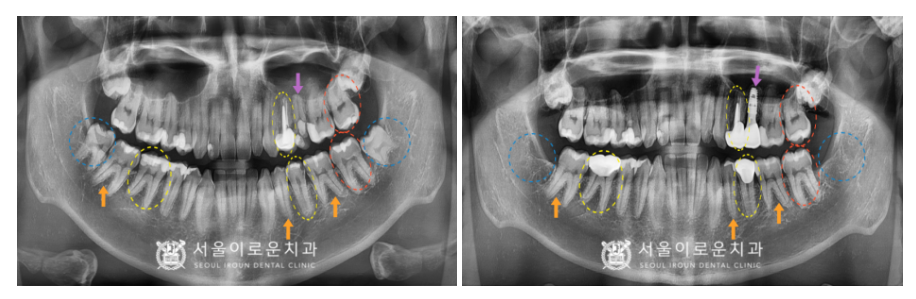

왼쪽 위 두 번째 작은 어금니(#25)는

발치 후 상악동 거상술을 동반하여

임플란트 즉시 식립을 하였습니다.

파노라마와 C T촬영을 통해

임플란트가 안정적으로

잘 식립 된 것을 확인하였으며,

식립 후 4개월 정도 충분한 시간을 가진 뒤

임플란트와 주변 치조골과의 결합이

단단히 되었는지 골 유착 정도를 확인하는

ossstell beacon이라는 장비를 이용하여

안정적인 것 확인하고

보철 과정을 진행하였습니다.

다른 보철 과정들도

환.자분의 식사나 불편함을 고려하여

순차적으로 진행해 드렸습니다.

부천시청역치과 서울이로운치과에서

모든 치.료가 마무리된 후 촬영한

파노라마 사진입니다.

임플란트 / 신경치료 / 크라운치료 /

인레이치료 / 발치를

모두 잘 도와드렸답니다.

✅ 전 > 후 ✅

(2023.02.03 ㅡ> 2023.08.26)